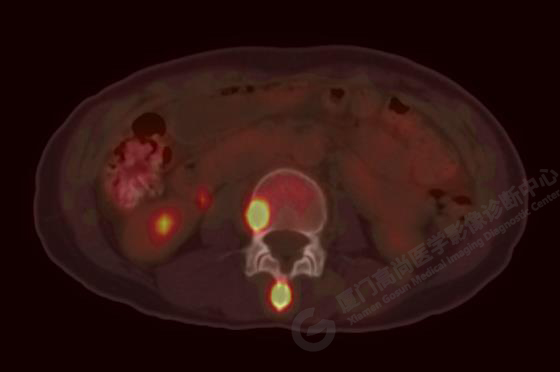

病例3:某女,47歲,咳嗽3周,無咯血,右上胸部疼痛,腰部疼痛

廈門市醫(yī)院查血腫瘤標記物,CA153、CA724、CA211、NSE、AFP、CEA、CA125均正常

右肺上葉前段實性腫塊,大小約3.2x2.7x2.6cm,邊緣見毛刺、分葉,胸膜牽拉明顯,前段支氣管阻塞。FDG攝取增高,SUVmax,16.8;右側(cè)頸部Ⅳ區(qū)、右側(cè)鎖骨區(qū)、右肺門及縱隔淋巴結(jié)腫大, FDG攝取增高,SUVmax7.9;C2、L2椎體、右側(cè)第6肋骨、骶骨、髂骨、左側(cè)髖臼、腰椎體及附件骨質(zhì)破壞,SUVmax11.8。

影像診斷:右肺上葉周圍型肺癌并多發(fā)淋巴結(jié)、骨骼轉(zhuǎn)移。(TNM分期,T2aN3M1c Ⅳ B期)

病理診斷:低分化腺癌